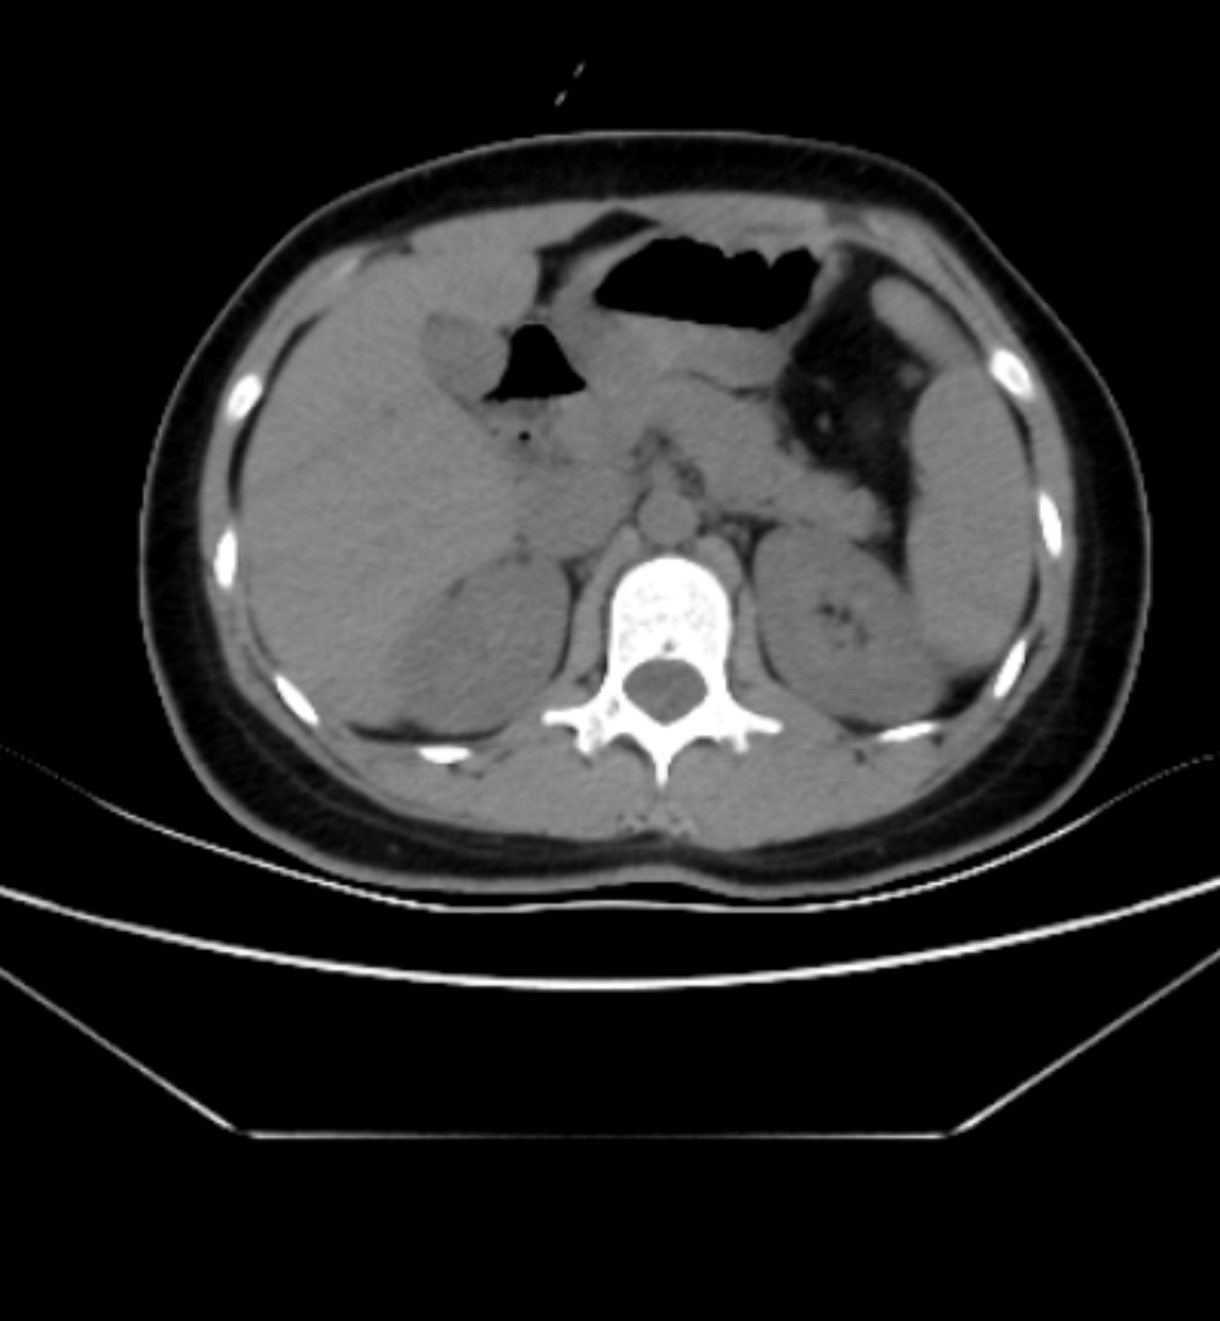

The patient, an 18-year-old woman, presented to the emergency department with a 24-h history of abdominal distension and discomfort accompanied by nausea and vomiting. The day prior to admission, she developed persistent epigastric distending pain of unknown etiology, associated with multiple episodes of nausea and vomiting. The emesis consisted of gastric contents, and there was no reported cessation of flatus or bowel movements. She initially sought medical attention at an external healthcare facility where conservative management for partial intestinal obstruction was initiated; however, her symptoms showed no significant improvement. Subsequently, she was transferred to our institution for comprehensive diagnostic evaluation and therapeutic intervention. Physical examination revealed a well-developed female adolescent with an acute, distressed facial expression. Cardiopulmonary auscultation demonstrated no abnormalities. Abdominal inspection showed a flat contour without visible gastrointestinal peristaltic waves. Palpation revealed positive tenderness in the epigastric region accompanied by rebound tenderness, but without significant abdominal wall rigidity. Auscultation demonstrated diminished bowel sounds. The patient’s medical history was non-contributory. Ancillary diagnostic investigations, specifically abdominal computed tomography (CT) scan, were performed. The rectal morphology appeared normal. However, there was localized twisting of the jejunal loops within the abdomen, accompanied by dilatation of the adjacent upper and lower intestinal segments, fluid accumulation, and swelling of the intestinal wall. The fat spaces surrounding the lesion exhibited a blurred appearance, with flocculent low-density shadows observed. Additionally, the mesentery was thickened, and multiple enlarged lymph nodes were present in the surrounding area (Figure 1).

Figure 1

Upon admission, the patient underwent an abdominal CT scan. The stomach (green arrow) and duodenum (the yellow dotted line section) are in normal positions. A narrow ring is formed at the site of the ligament of Treitz (black arrow); the herniated part (the white dotted line section) and the distal intestinal segment (the red dotted line section) present a dumbbell shape.